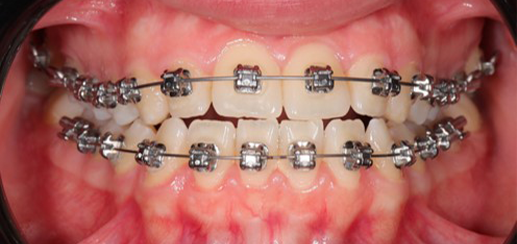

A 22-year-old female patient presented with a Class III malocclusion. She does not like her own profile. Her facial profile was straight with a slightly retrusive maxilla, the upper incisors were within normal inclination, and the lower incisors were retroclined. Bolton discrepency is on mandible for 6 teeth. A retruded upper lip and a normally positioned lower lip were noted. There was also a marked lack of midface support, and the constricted dental arches resulted in a narrow smile and pronounced dark buccal corridors.

At the end of treatment, the patient’s occlusion was corrected to Class I molar and canine relationships with a physiological overjet and overbite. Irregularities in both arches were eliminated, arch forms were coordinated, and incisor torque was effectively controlled to position the roots centrally within the alveolar bone, enhancing stability. Satisfactory intercuspation was achieved in both the anterior and posterior segments, with maintenance of midline coincidence and periodontal health throughout treatment. The case was finished and transitioned into the retention phase using fixed retainers in the maxillary and mandibular anterior regions.